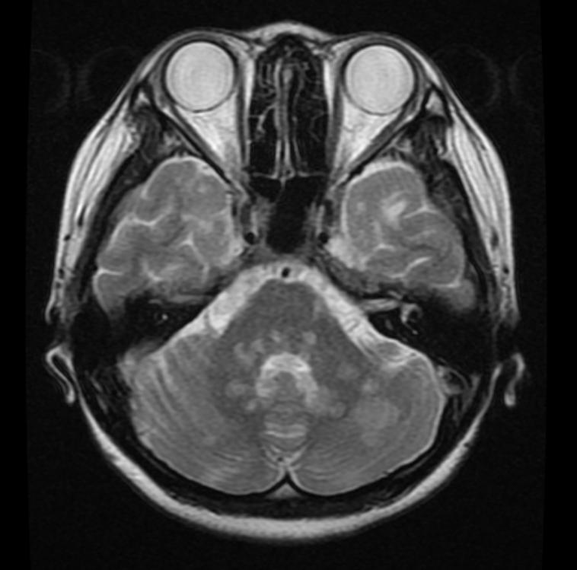

小脳梗塞(急性期)の頭部MRI(T2強調像、水平断)

左小脳半球と一部右小脳半球に高信号域を認める。